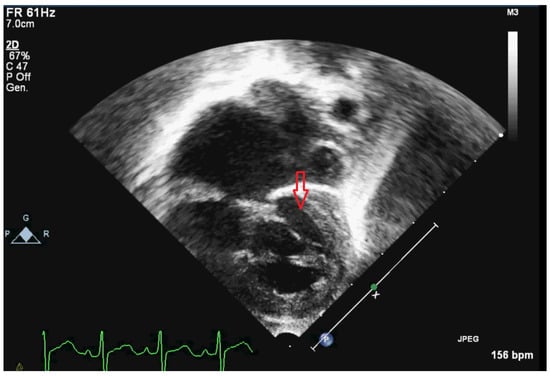

| Cardiovascular defects | HLHS with mitral-aortic atresia (normal origin of the coronary arteries) |